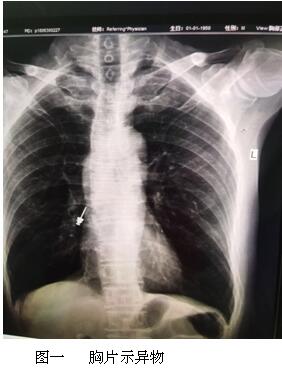

六月最后一天的上午,內(nèi)鏡中心來了一名特殊的患者,患者表情焦慮,訴于外院補(bǔ)牙時(shí),不小心把補(bǔ)牙的一顆螺絲吞下,現(xiàn)咽喉部明顯不適,于我院耳鼻喉行喉鏡檢查,未見明顯異物,內(nèi)鏡中心伍友興主任聽聞后,考慮異物可能卡在食管上段,持鏡給予患者行胃鏡檢查,但是反復(fù)觀察食道、胃及十二指腸,并未找到患者所描述的異物。是不是有可能異物已經(jīng)掉入十二指腸以下的消化道了呢?如果已經(jīng)掉入小腸,這一顆大約長(zhǎng)2cm的螺絲,表面無明顯銳利邊緣,刺破腸管的可能性較小,可自行隨大便排出,正當(dāng)我們準(zhǔn)備松一口氣告訴患者胃鏡下未見明顯異物時(shí),患者輕輕的咳嗽兩聲引起了伍主任的注意,“快去行胸部照片,異物可能掉入氣管”伍主任說到,患者遂行胸部照片,見異物果然出現(xiàn)在患者右側(cè)的肺里,為進(jìn)一步確定異物部位,給予行胸部CT檢查,并積極聯(lián)系呼吸內(nèi)科豐偉民主任,黃雪英老師與豐主任兩人密切配合,在支氣管鏡下看到右側(cè)支氣管下段,找到了讓人揪心的異物,順利取出,此刻患者緊縮的眉頭終于舒展開來,連連向我們醫(yī)務(wù)人員道謝。